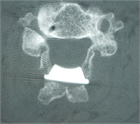

1. 透析脊椎症の重症度以上に、全身合併症の重症度評価が手術適応、術式選択に際して重要。